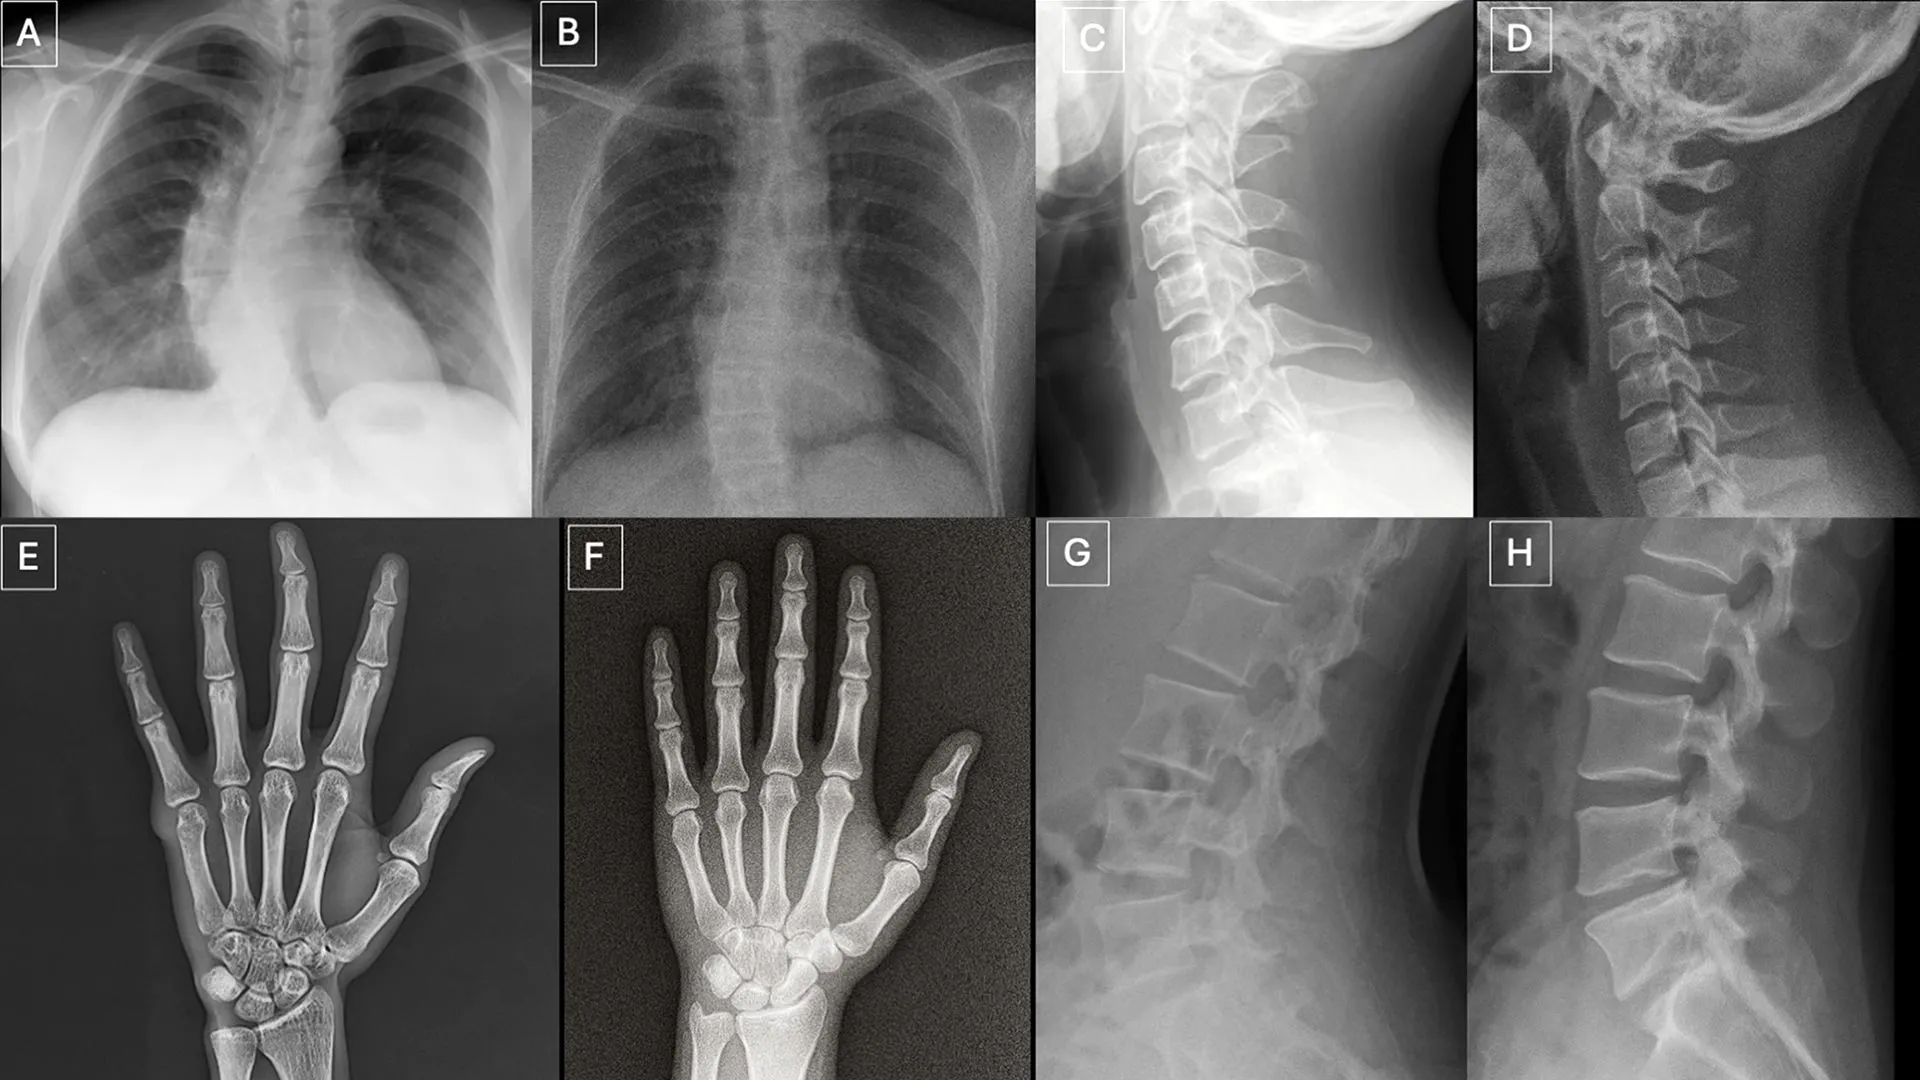

Deepfake X-rays are so real even doctors can't tell the difference

A new study published in Radiology shows that both radiologists and multimodal large language models (LLMs) have difficulty distinguishing real X-rays from AI-generated "deepfake" images. The study examined 264 X-ray images split evenly between real scans and AI-generated ones, revealing that radiologists could only identify AI-generated X-rays 41% of the time when not told fake images were present.

When radiologists were specifically told that AI-generated images were included in the test set, their accuracy improved but still varied significantly depending on the type of X-ray. For chest X-rays generated by RoentGen, radiologists achieved accuracy rates between 62% and 78%, while AI models ranged from 52% to 89%. The study raises important concerns about the potential for medical imaging fraud and the need for robust detection systems.